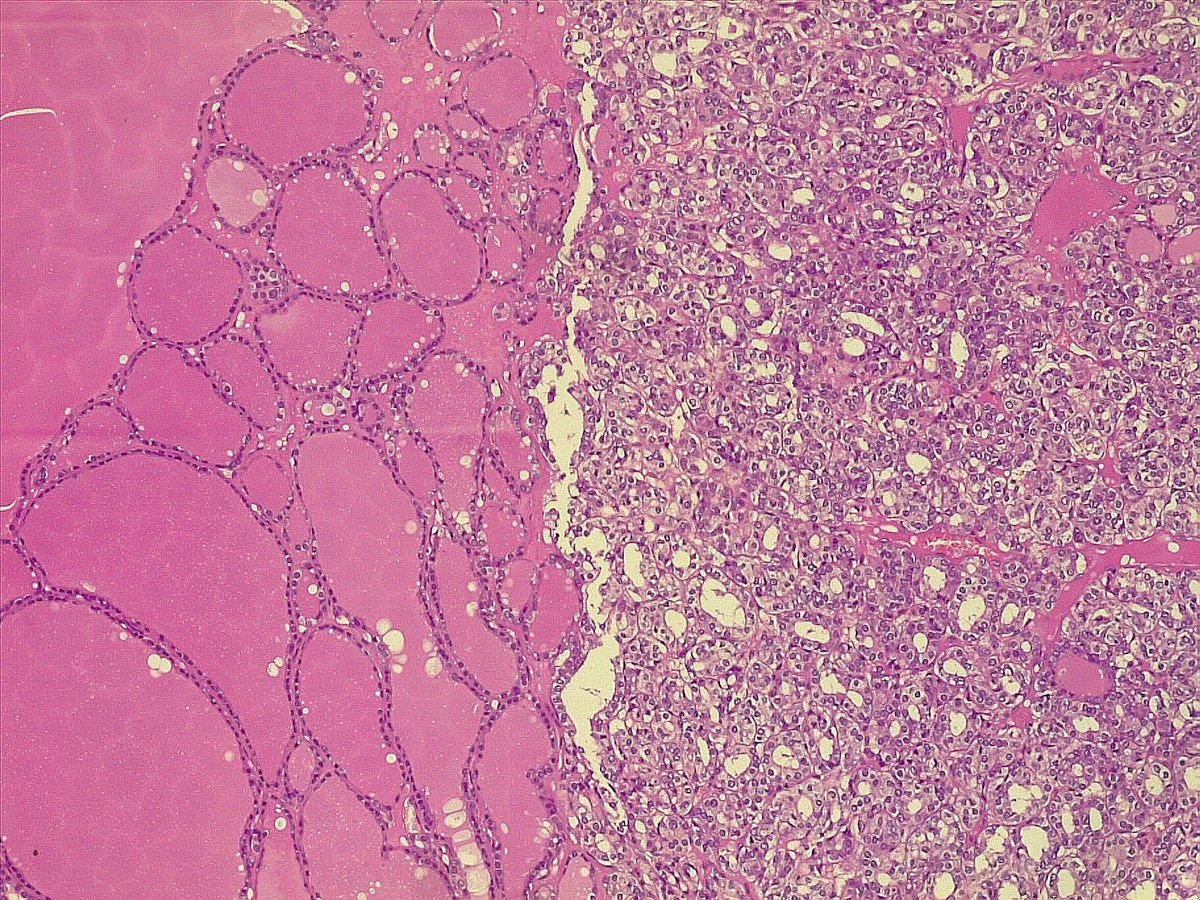

What’s the diagnosis of this spindle cell lesion of breast? 🪡🔬 Poll in the comments 👇 Answer reveal on Monday! 🙌 #PathX #PathTwitter #breastpath